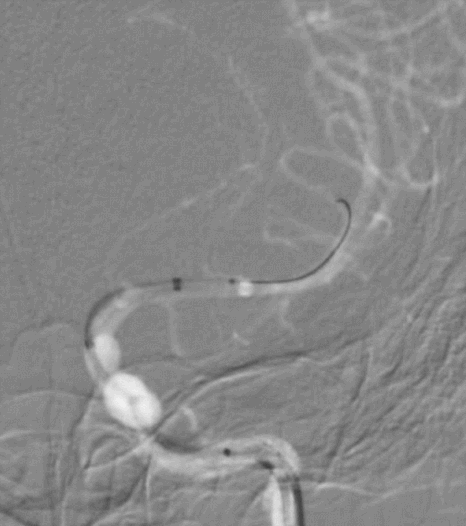

4mm×30mm Streamline

术后4月余随访:多发动脉瘤均未见显影,远端残余轻度狭窄

术前术后对比